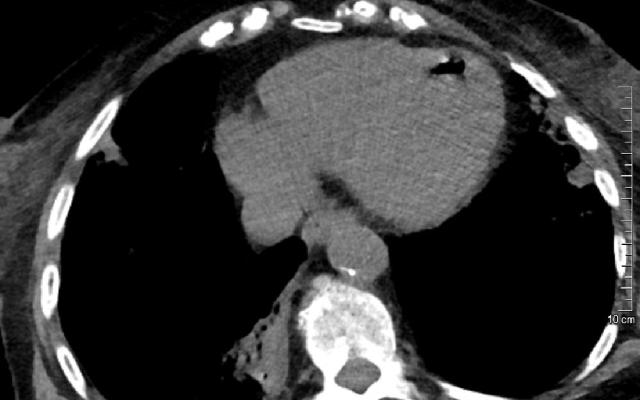

Tijdens deze behandeling wordt de omgevingsdruk langzaam opgebouwd naar 2,4 bar, horen we als we worden rondgeleid door Rob van Hulst, Nederlands enige hoogleraar Hyperbare en Duikgeneeskunde. Dat komt overeen met de druk die je 14 meter onder water ervaart. Tegelijkertijd krijgen de patiënten via een masker 100% zuurstof toegediend. Hierdoor stijgt de zuurstofsaturatie in het bloed en krijgen organen en…